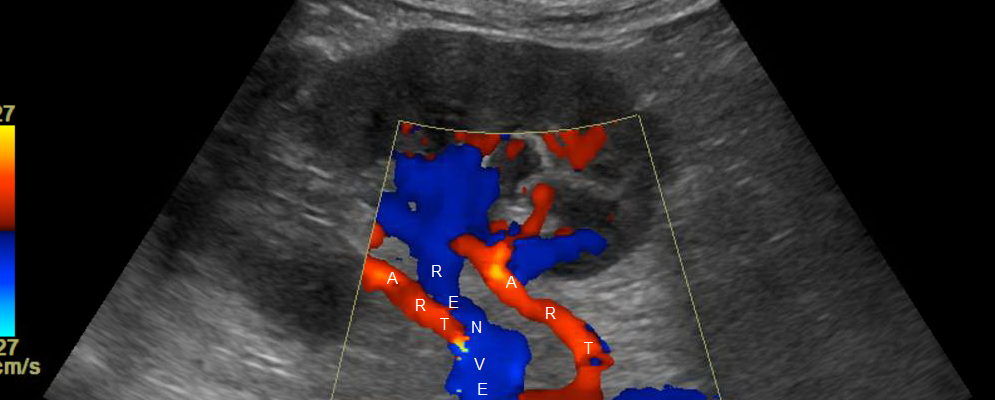

Renal artery disease, often a silent predator, can lead to severe kidney damage and hypertension if left undiagnosed. The Renal Artery Color Doppler is a non-invasive ultrasound technique that provides a detailed view of the renal arteries, helping doctors detect blockages or abnormalities early on. This diagnostic tool plays a crucial role in preventing the progression of kidney-related diseases, offering a practical solution to one of the major health issues faced by individuals today.

After consulting with Dr. Mehta, a renowned nephrologist in Mumbai, Rajesh underwent a Renal Artery Color Doppler test. The results revealed significant narrowing in his renal arteries—a condition known as renal artery stenosis. Dr. Mehta explained that if not addressed promptly, this could lead to chronic kidney disease or uncontrolled high blood pressure. Thanks to the early detection, Rajesh was able to start treatment immediately, drastically reducing the risk of further complications.